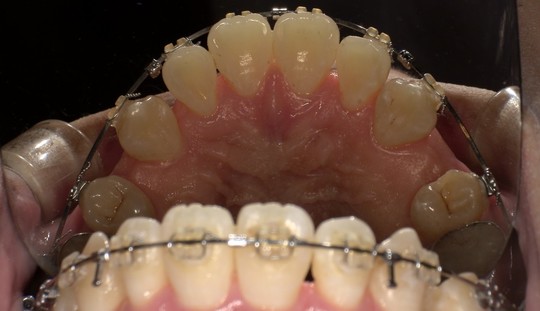

ステイン除去

BEFORE

AFTER

年齢:70代男性

治療内容:エアーフローによる歯の着色汚れ、ステイン除去

治療期間/通院回数:1回

費用: ステインコース 8,800円